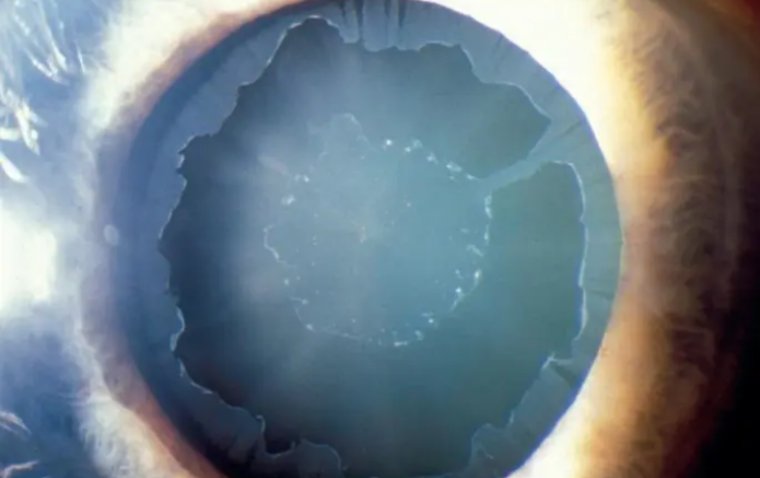

Офтальмологический скрининг: обязательная диагностика к 40 годам

Американская академия офтальмологии опубликовала рекомендацию: взрослым до 40 лет необходимо проходить скрининг глазных болезней каждые 5–10 лет. К 40 годам …